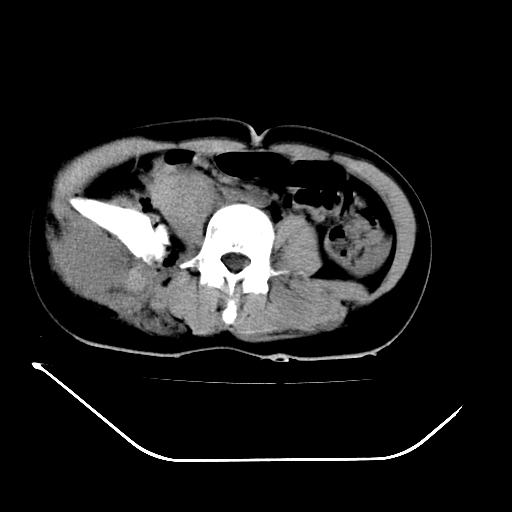

以下是引用liuyue在2008-7-19 13:02:00的发言:[br]1.肝右叶后下段及右肾挫裂伤伴腹腔积血。[br]2.右侧多发性肋骨骨折、横突骨折、右髂骨骨折伴周围软组织挫伤。[br]3.右侧腰大肌肿胀,并可见低密度影,如为气体,则肠道挫裂伤待除外。

以下是引用zhengfaming在2008-7-19 14:42:00的发言:[br]1.肝右叶后下段及右肾挫裂伤伴腹腔积血。脾脏挫裂伤待排[br]2.右侧多发性肋骨骨折、横突骨折、右髂骨骨折伴周围软组织挫伤。[br]3.右侧腰大肌肿胀,并可见低密度影,如为气体,则肠道挫裂伤待除外

以下是引用道哥在2008-7-19 16:52:00的发言:[br]肝右叶后下段及右肾挫裂伤、脾破裂伴腹腔积血。[br]2.双侧多发性肋骨骨折、横突骨折、右髂骨骨折伴周围软组织挫伤。[br]3.右侧腰大肌肿胀,并可见低密度影,如为气体,则肠道挫裂伤待除外。